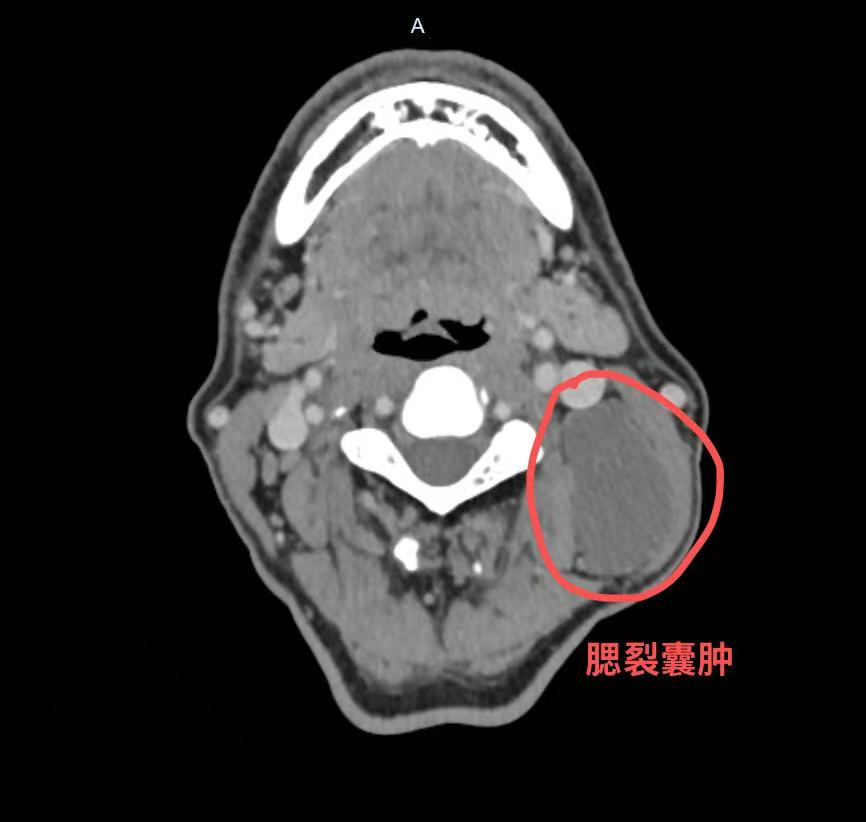

一年前,患者无意中摸到左侧颈部有一个鹌鹑蛋大小的软包,不痛不痒,大小还会变化——平时不明显,可一感冒就“鼓”起来。因为不疼不痒,他也没太在意。直到最近三个月,这个包块突然长大,还伴随吞咽不适,他才匆匆来到市中医医院普外科就诊。颈部彩超和增强CT检查后,谜底揭晓:他得的是一种叫做“腮裂囊肿”的先天性疾病。

这其实是一种先天发育异常。在胚胎时期,我们的颈部两侧曾有类似鱼鳃的结构,称为“鳃裂”。正常情况下,这些结构会随着发育完全闭合消失。如果闭合不全,残留的上皮组织就会形成囊肿,也就是腮裂囊肿。它就像颈部埋下的一颗“定时炸弹”,平时可能相安无事,一旦身体抵抗力下降(如感冒、劳累),就可能继发感染,出现红、肿、热、痛,甚至形成瘘管,反复流脓,经久不愈。